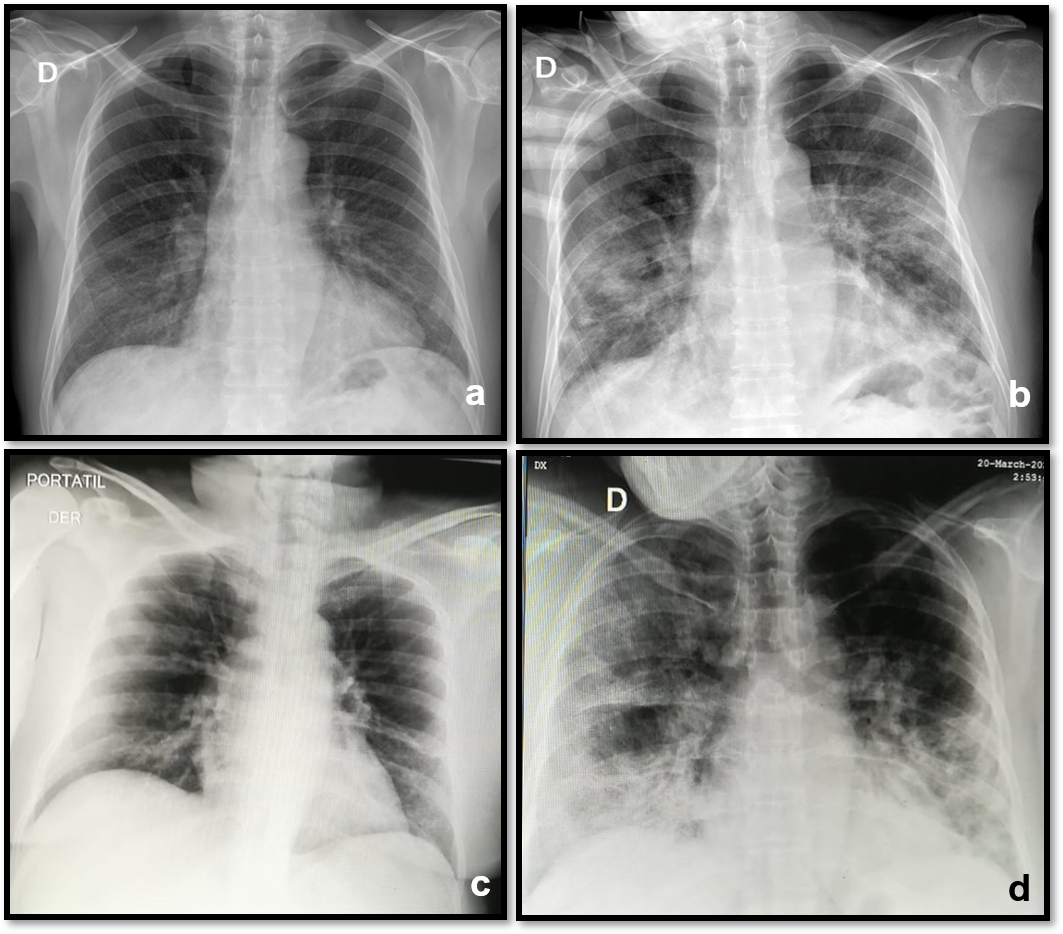

Chest x-rays were performed on 86 patients during the admission, all with bilateral opacity. None presented pleural effusion (Figure 1).

Figure 1 Chest x-ray with the evolution of two patients. a).- Male. 59 years old. March 25. At admission: Interstitial lung pattern in lower zones with right predominance. b).- March 31. in ICU: Right alveolar opacities in mid and lower zones Left hazy opacity in mid and lower zones. Dyspnea got worse and required invasive mechanical ventilation. Dies 14 days later. c).- Female. 59 years old. March 18. At admission: Lower vague hazy densities. d).- March 20. in ICU: Bilateral diffuse interstitial pattern with ground glass opacities in the right upper and lower areas. Greater lower right opacity due to peribronchovascular thickening. Dyspnea got worse and required invasive mechanical ventilation. She had a full recovery and was discharged 23 days later.